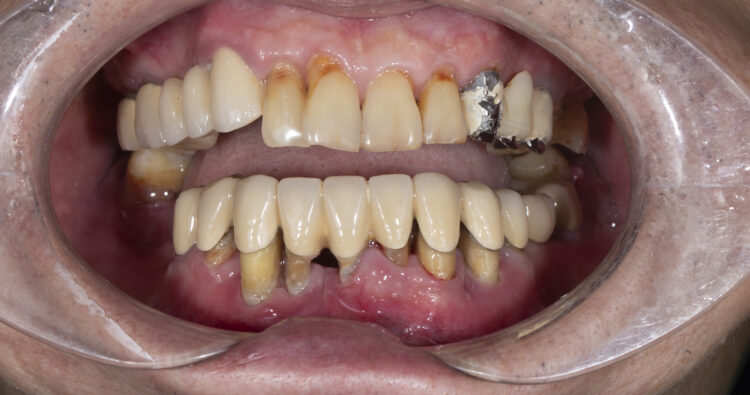

Tại Nha khoa Olympia, các cô chú/anh chị mất răng đến thăm khám kiểm tra tình trạng răng đã làm cầu răng sứ bị hỏng: ...[Xem thêm]